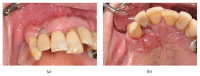

Purpose. Implant therapy plays an important role in contemporary dentistry with high rates of long-term success. However, in recent years, the incidence of peri-implantitis and implant failures has significantly increased. The peripheral giant cell granuloma (PGCG) rarely occurs in peri-implant tissues and it is clinically comparable to the lesions associated with natural teeth. Therefore, the study of possible diseases associated with dental implants plays an important role in order to be able to diagnose and treat these conditions. Materials and Methods. This report described a 60-year-old Caucasian male who presented a reddish-purple pedunculated mass, of about 2 cm in diameter, associated with a dental implant and the adjacent natural tooth. Results. An excisional biopsy was performed and the dental implant was not removed. Histological examination provided the diagnosis of PGCG. After 19-month follow-up, there were no signs of recurrence of peri-implantitis around the implant. Conclusion. The correct diagnosis and appropriate surgical treatment of peri-implant giant cell granuloma are very important for a proper management of the lesion in order to preserve the implant prosthetic rehabilitation and prevent recurrences.